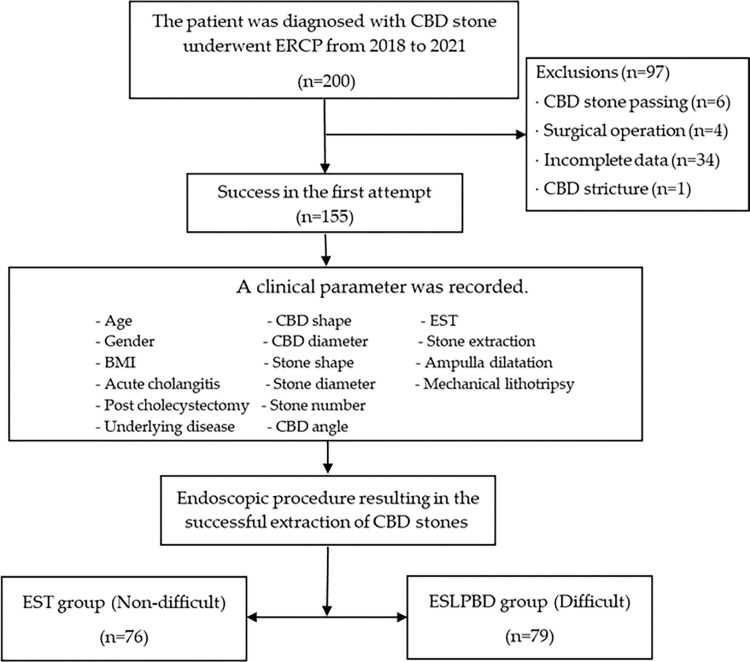

During the study period, 200 patients diagnosed with CBD stones underwent endoscopic treatment were collected. The final analysis included 155 patients, as illustrated in Fig 1. There were 111 (71.61%) females and 44 (28.39%) males. Their median age was 52 years (IQR = 37.0–70.0). Additionally, 34 (21.94%) participants had periampulla diverticulum, 22(14.19%) participants were previous cholecystectomies, and 58 (37.42%) participants had acute cholangitis at the first ERCP session.

The participants were divided into two groups: 76 (49.03%) patients were in the non-difficult group defined as having the successful stone extraction by endoscopic sphincterotomy plus stone extraction and 79 (50.97%) patients were in the difficult group defined as having successful stone extraction by additional EPLBD combined with EST plus stone extraction. The success rate for the non-difficult group in the first session was 73.68%, whereas the success rate for the difficult group was 44.30%. In the non-difficult group, the median of overall session attempts until success is 1 session (IQR = 1.0, 2.0), and in the difficult group, it is 2 sessions (IQR = 1.0, 2.0).